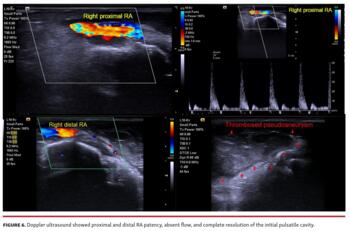

Six days later, she noticed subtle and rapidly progressive wrist, hand, and finger swelling, with pain, ecchymosis, and movement limitation. Physical examination evidenced pulsatile mass, thrill, and murmur, compatible with pseudoaneurysm (Figure 1). Doppler ultrasound (US) evidenced a huge cavity with whirlwind flow and spontaneous contrast communicating with the right distal radial artery (RA) (Video 1). After continuous 30-minute US-guided pseudoaneurysm’s neck compression (Figure 2), no pulsatile mass, thrill, murmur, whirlwind flow, or Doppler pulses were detected. One-week follow-up evidenced recurrence of pulsatile mass (Video 2), thrill, and murmur, compatible with pseudoaneurysm recidivism (Figure 3), confirmed by Doppler US (Figure 4; Videos 3 and 4). Following pseudoaneurysm neck precise location, a TR band was placed and inflated with 20 mL of air (Figure 5, Video 5). After 4 hours, Doppler US showed proximal and distal RA patency, absent flow, and complete resolution of the initial pulsatile cavity (Figure 6, Video 6). During TR band inflation and after its removal, pulse oximetry in all digits was ≥95% (Figure 7). Physical examination and Doppler US at 30 and at 120 days (Figure 8) after index procedures corroborated pseudoaneurysm resolution.